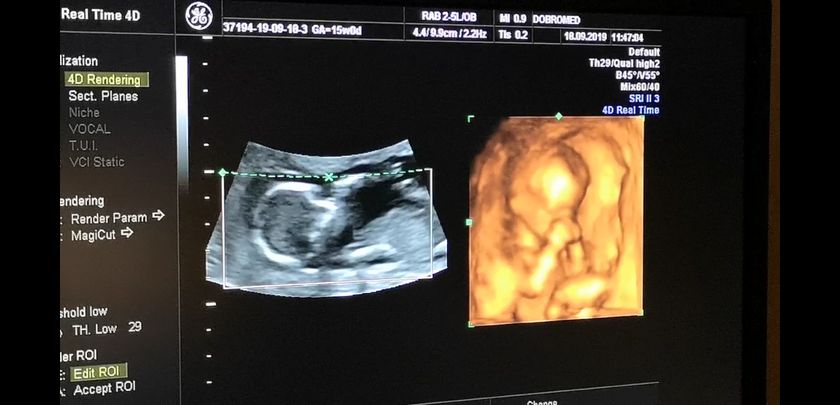

14 недель и 7 дней, нам врач сказала что точно видно мошонку и это мальчик… но я не уверена ? у него пуповина между ног была, короче я запуталась.

На 1 скрининге нам предположили что будет девочка, а тут сюрприз вырос....... Может всё таки пуповина? ?

Ну у вас только 15 недель, мне 100% сказали пол в 19 недель. На 2ом узи. Чуть подождите.

На 2-ом скрининге скажут точно